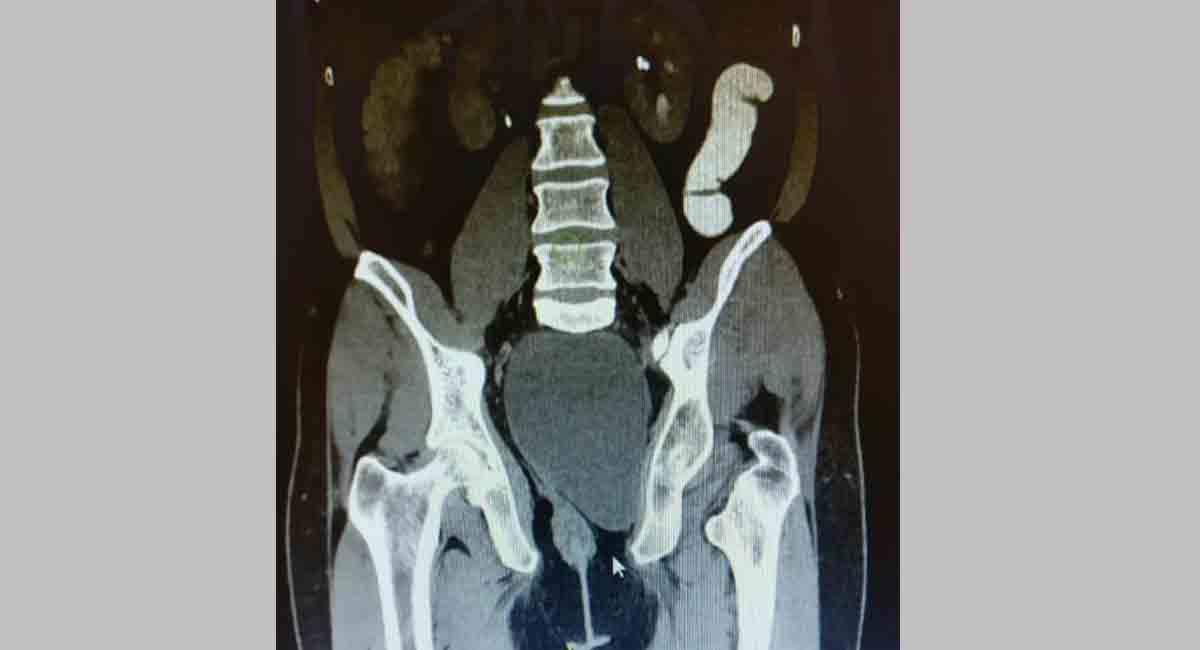

Hyderabad: Surgeons at Krishna Institute of Medical Science (KIMS), Kondapur on Sunday said they have successfully treated a 47-year-old person, who had a congenital cyst in his pelvic region that was blocking the patient to pass urine and motions.

The patient who hails from Guntur was catheterized multiple times in local hospitals to remove urine but his medical condition kept persisting. Later, he was admitted to KIMS, Kondapur under the care of senior surgical gastroenterologist, Dr DV Ramakrishna.

“Investigations revealed that he had a large cyst in the pelvis, which was blocking the urine and motion. Known as Tail Gut Cyst, a congenital disorder, the cyst was 7 cms x 4 cms in size and occupying the whole pelvis and disrupting the pelvic floor muscles on the left side with an extension of the cyst into the left thigh,” Dr Ramakrishna said.

The patient underwent a surgery last November and the cyst was completely removed including the part, which extended into the thigh. A three month follow-up revealed a complete recovery with no loss of sexual, urinary or bowel function.